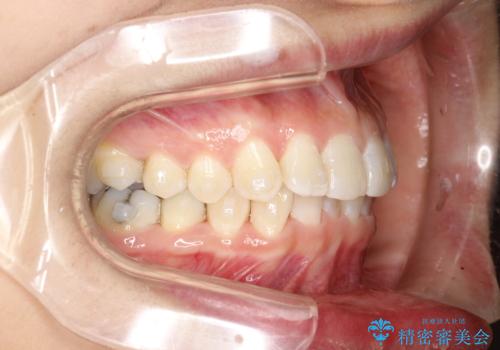

前歯のガタガタをインビザラインで矯正

- 前歯のがたつきを気にされて来院されました。

右上の前から2番目の歯が前方に大きく傾いており、下の前歯もガタガタしていました。

インビザラインにて、歯と歯のあいだをわずかに削り並べる計画としました。

しっかりとマウスピースを使用していただけたので、順調に治療を終えることができました